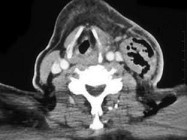

- 单项选择题患者食道部分切除术后,影像检查如图, 最可能的诊断是 ( )

A、脓肿

B、正常术后改变

C、肌肉坏死

D、纤维神经瘤

E、淋巴瘤